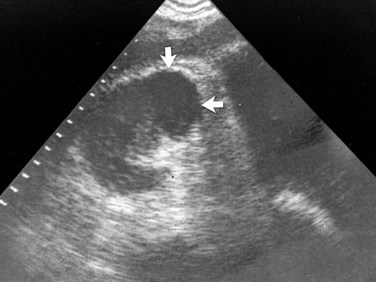

Acute focal or multifocal bacterial nephritis is an uncommon, severe form of acute renal infection in which a heavy leukocyte infiltrate is confined to a single renal lobe (focal) or multiple lobes (multifocal).

The diagnosis must be made by radiologic examination. The mass has slightly less nephrographic density than the surrounding normal renal parenchyma.

Ultrasonography and CT establish the diagnosis. On ultrasonography the lesion is typically poorly marginated and relatively sonolucent with occasional low-amplitude echoes that disrupt the cortical medullary junction (Corriere and Sandler, 1982) (Fig. 10–21A). Enhancement with a contrast agent is necessary with CT studies because the lesion is difficult to visualize on the unenhanced study (see Fig. 10–21B). Wedge-shaped areas of decreased enhancement are seen. No definite wall is evident, and frank liquefaction is absent. Conversely, abscesses tend to have liquid centers, are usually round, and are present both before and after contrast medium enhancement. More chronic abscesses may also show a ring-shaped area of increased enhancement surrounding the lesion (Corriere and Sandler, 1982). Gallium scanning reveals uptake that is in the region of and larger than the previously demonstrated mass (Rosenfield et al, 1979). In patients with multifocal disease the findings are similar but multiple lobes are involved.

Figure 10–21 Acute focal bacterial nephritis. A, Ultrasound image: longitudinal view of the left kidney demonstrates spleen (S) and left kidney (arrows). Note irregular midpole mass (M) of slightly higher echo texture than surrounding normal renal parenchyma. B, Contrast medium–enhanced CT scan demonstrates a wedge-shaped area of low density (arrows) in the middle portion of the left kidney. The findings resolved after antimicrobial therapy.

(From Schaeffer AJ. Urinary tract infections. In: Gillenwater JY et al, editors. Adult and pediatric urology. Philadelphia: Lippincott Williams & Wilkins; 2002. p. 211–72.)

Acute bacterial nephritis probably represents a relatively early phase of frank abscess formation. In a series of cases reported by Lee and coworkers (1980) a patient with acute focal bacterial nephritis progressed to abscess formation. Treatment includes hydration and intravenous antimicrobial agents for at least 7 days, followed by 7 days of oral antimicrobial therapy. Patients with bacterial nephritis typically respond to medical therapy, and follow-up studies will show resolution of the wedge-shaped zones of diminished attenuation. Failure to respond to antimicrobial therapy is an indication for appropriate studies to rule out obstructive uropathy, renal or perirenal abscess, renal carcinoma, or acute renal vein thrombosis. Long-term follow-up studies performed in a few patients with multifocal disease have demonstrated a decrease in renal size and focal calyceal deformities suggestive of papillary necrosis (Davidson and Talner, 1978).